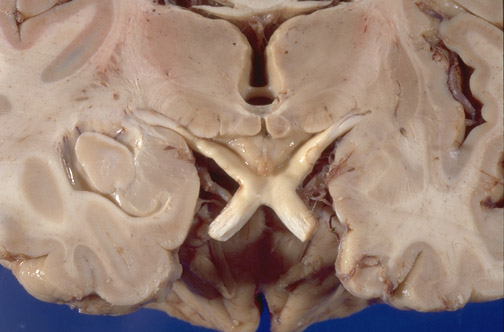

Identify the following structures in the image above: Optic chiasm - Optic tract - Third ventricle -